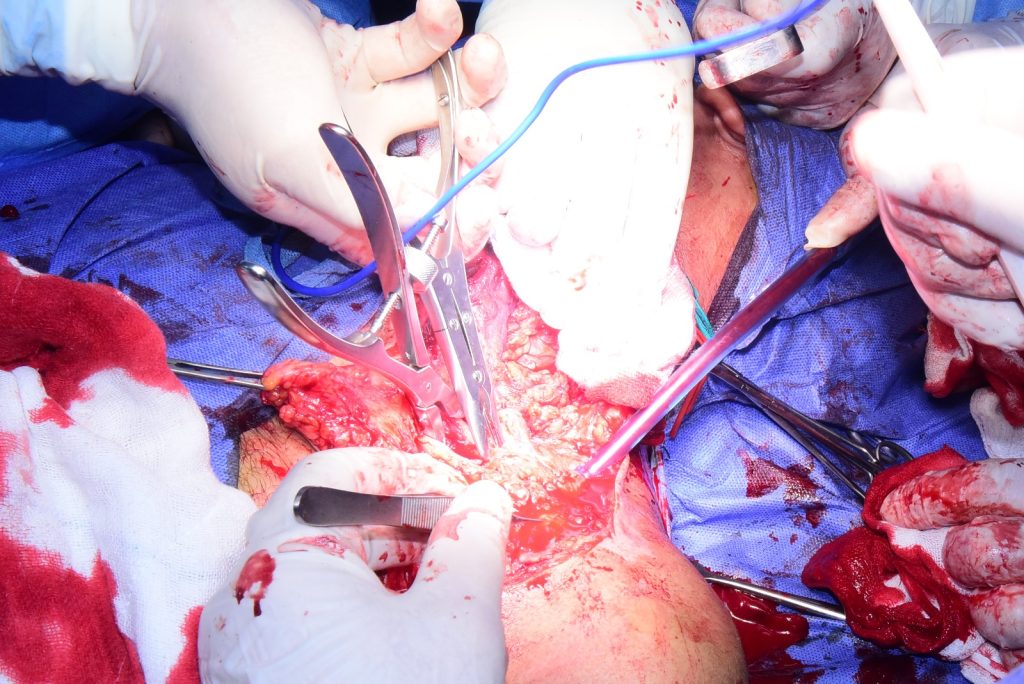

يواصل الدكتور حسان النعماني رئيس جامعة سوهاج واستاذ جراحة اليد والجراحات الميكروسكوبية والفريق الطبي المصاحب له إجراء العمليات الجراحية المعقدة لحاله مصابه بتهتك الضفيرة العصبية، اثر حادث سيارة ادي الي شلل تام للطرف العلوي الايسر، حيث تعد هذه العملية انجاز جديد يضاف لنجاحات الوحده في علاج الحالات المعقدة الصعبة ذات المهارة العاليه، والتي تم اجرائها بوحدة جراحة اليد والجراحات الميكروسكوبية بالمستشفى الجامعي القديم.

وأوضح النعماتي انه خلال العمليه تم استكشاف للضفيرة العصبية و تبين وجود تهتك بها مع فقد الجزء الواصل بين الحبل الشوكي العنقي والطرف الاخر من الضفيرة، وقد تم اجراء ترقيع عصبي تعويضا للجزء المفقود، حيث ان الحاله كانت مصابة بتهتك الضفيرة العصبية المغذية للطرف العلوي الايسر والذي ادي الي شلل تام للطرف العلوي الايسر، مضيفا ان التدخل الجراحي استمر علي مدار ٥ ساعات، بوحدة جراحة اليد والجراحات الميكروسكوبية بمستشفى الأورام بالمستشفيات الجامعية.